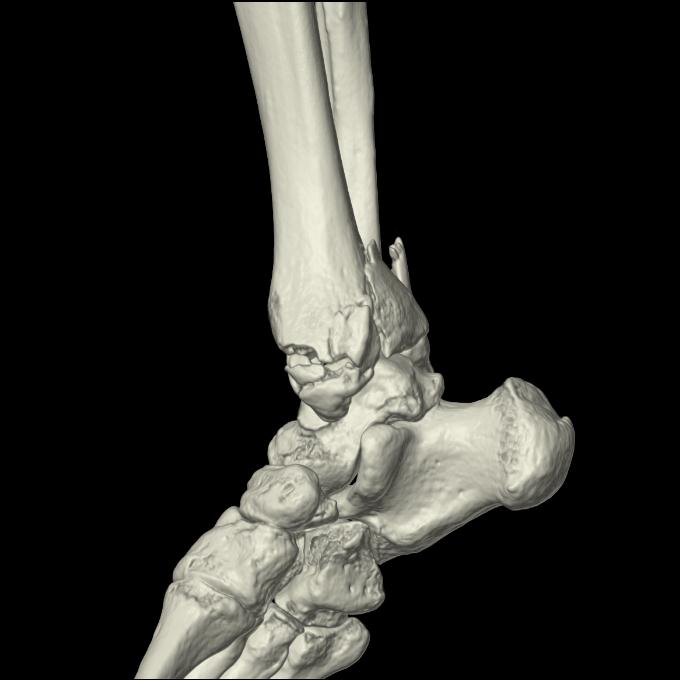

102755 1/4 2R 1/15 2R 右足関節 68歳女性 右三果脱臼骨折